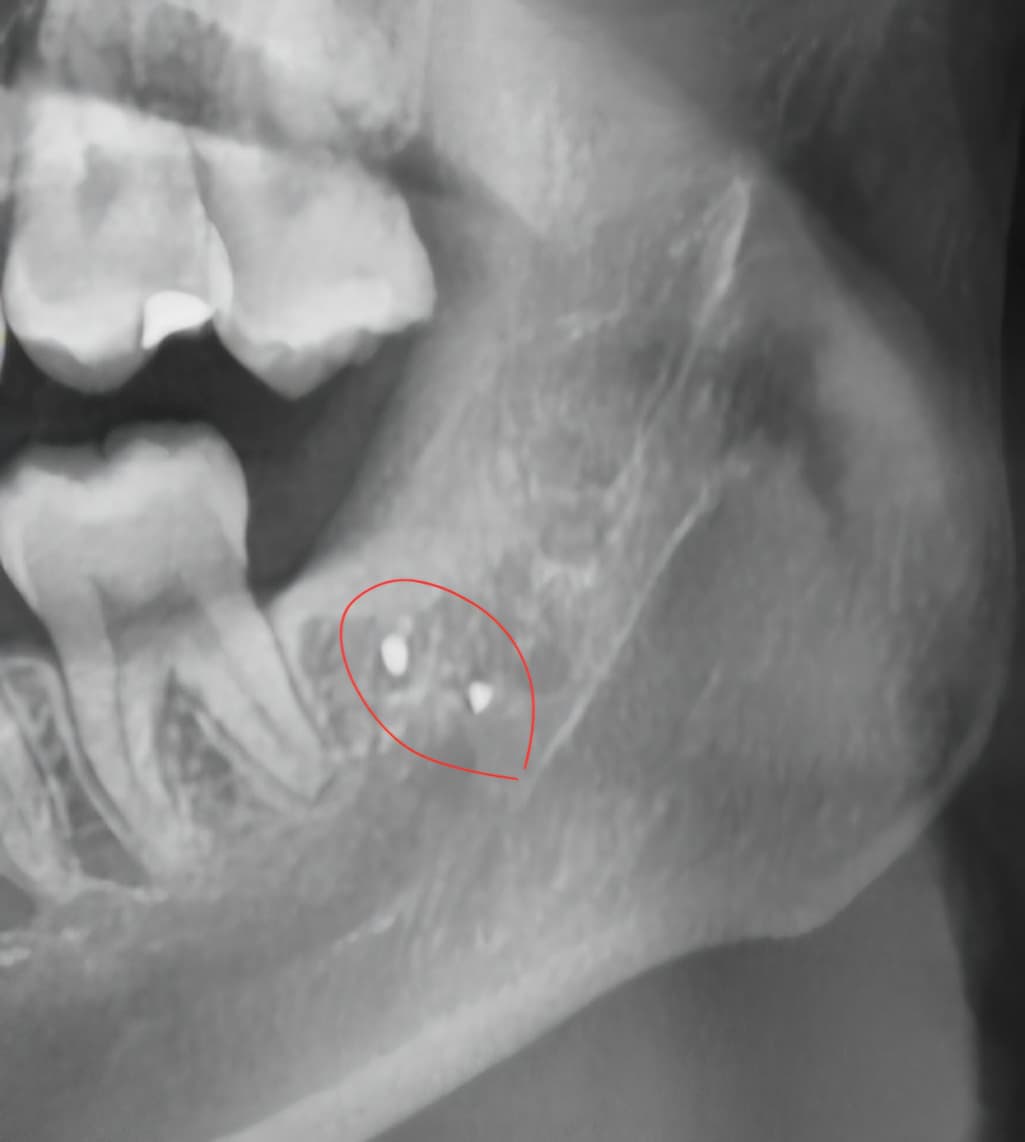

사랑니 뽑은 지 9개월이 넘었고, 같은 치과에서 엑스레이를 찍었더니 사진과 같은 게 있었습니다

사랑니를 발치하는 과정에서 아말감이 탈락되어 들어갔거나 도구가 파절되었다면 해당부위에 방사선 사진상처럼 보일수 있습니다. 감염이 되지 않았다면 문제가 되지 않으며 무리하게 제거를 하려고 하면 신경손상등이 발생할수 있습니다.

증상이 없다면 그냥 두셔도 크게 문제가 되진 않습니다. 오히려 저걸 제거하려다가 신경손상 가능성이 있어 보입니다.

1 .작은 이물질이고 특별히 그동안 이물질을 일으키지 않았다면 이로 인해 문제가 발생할 확률은 낮습니다

저걸 빼기 위해 잇몸뼈를 삭제하고, 신경을 건드릴 가능성이 있기 때문에 득보다 실이 클 수 있습니다